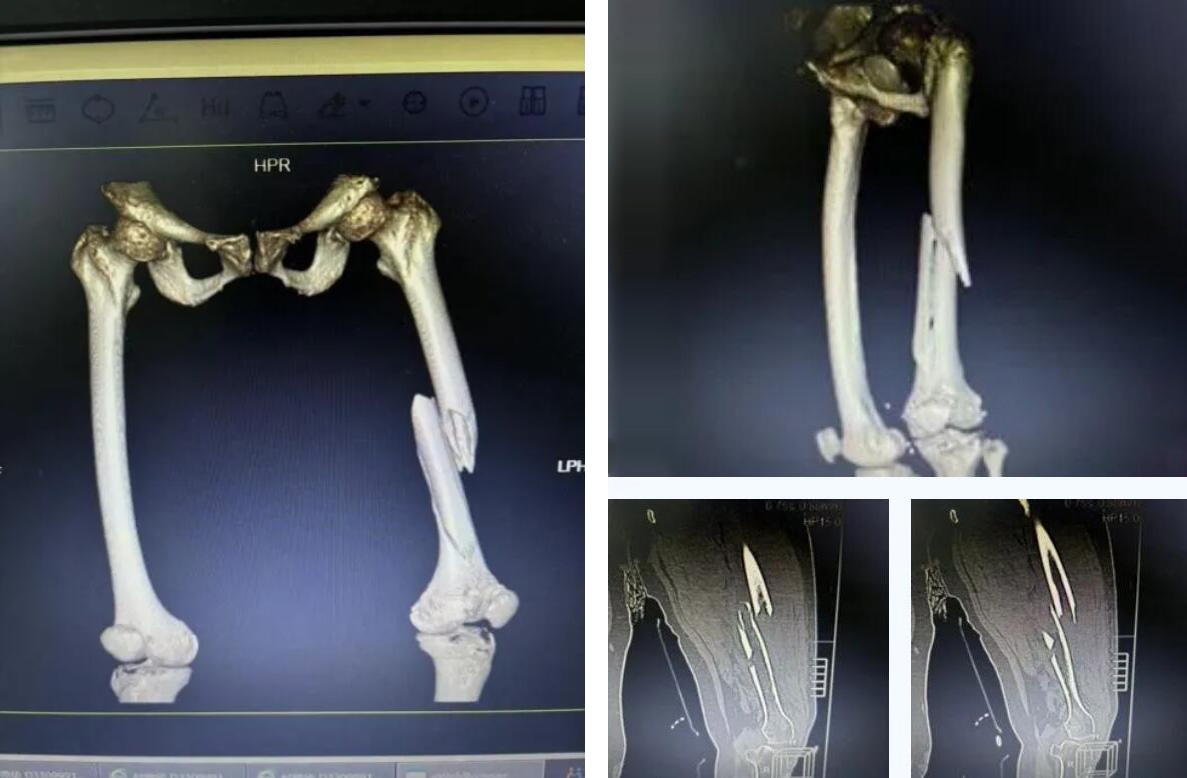

术前患者骨折CT影像

经检查确诊为 “右股骨多段粉碎性骨折”。考虑到俞奶奶年事已高,身体机能衰退,当地医院认为手术风险极大,建议转院治疗。